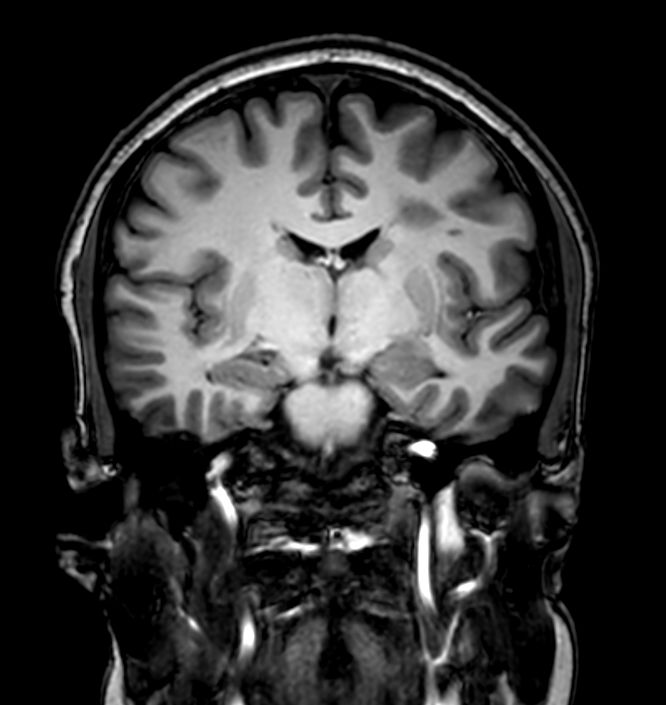

3D VIEW - T2w FLAIR (coronal reformat)

-